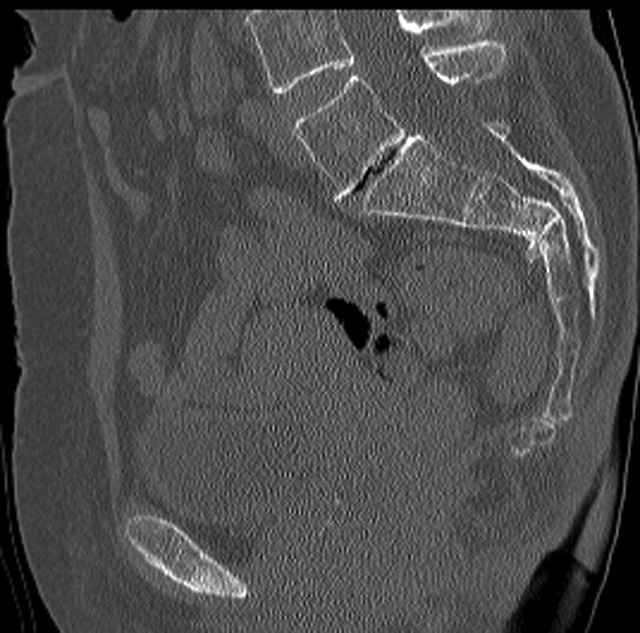

Pelvic CT Scan - 3 Months After Fall

Sacral Injuries

Ramus Fractures